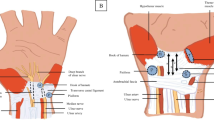

To assess the discriminative power of radiomics of peripheral nerves at 1.5T MRI, using common entrapment neuropathies of the upper limb as a model system of focal nerve injury.

Features analysis demonstrated statistically significant differences between normal and pathological nerve. The results suggested that radiomics analysis could assess the median and ulnar nerve inner structure changes due to the loss of the fascicular pattern, intraneural edema, fibrosis or fascicular alterations in mild carpal tunnel and mild cubital tunnel syndromes even when the nerve cross-sectional area does not change.